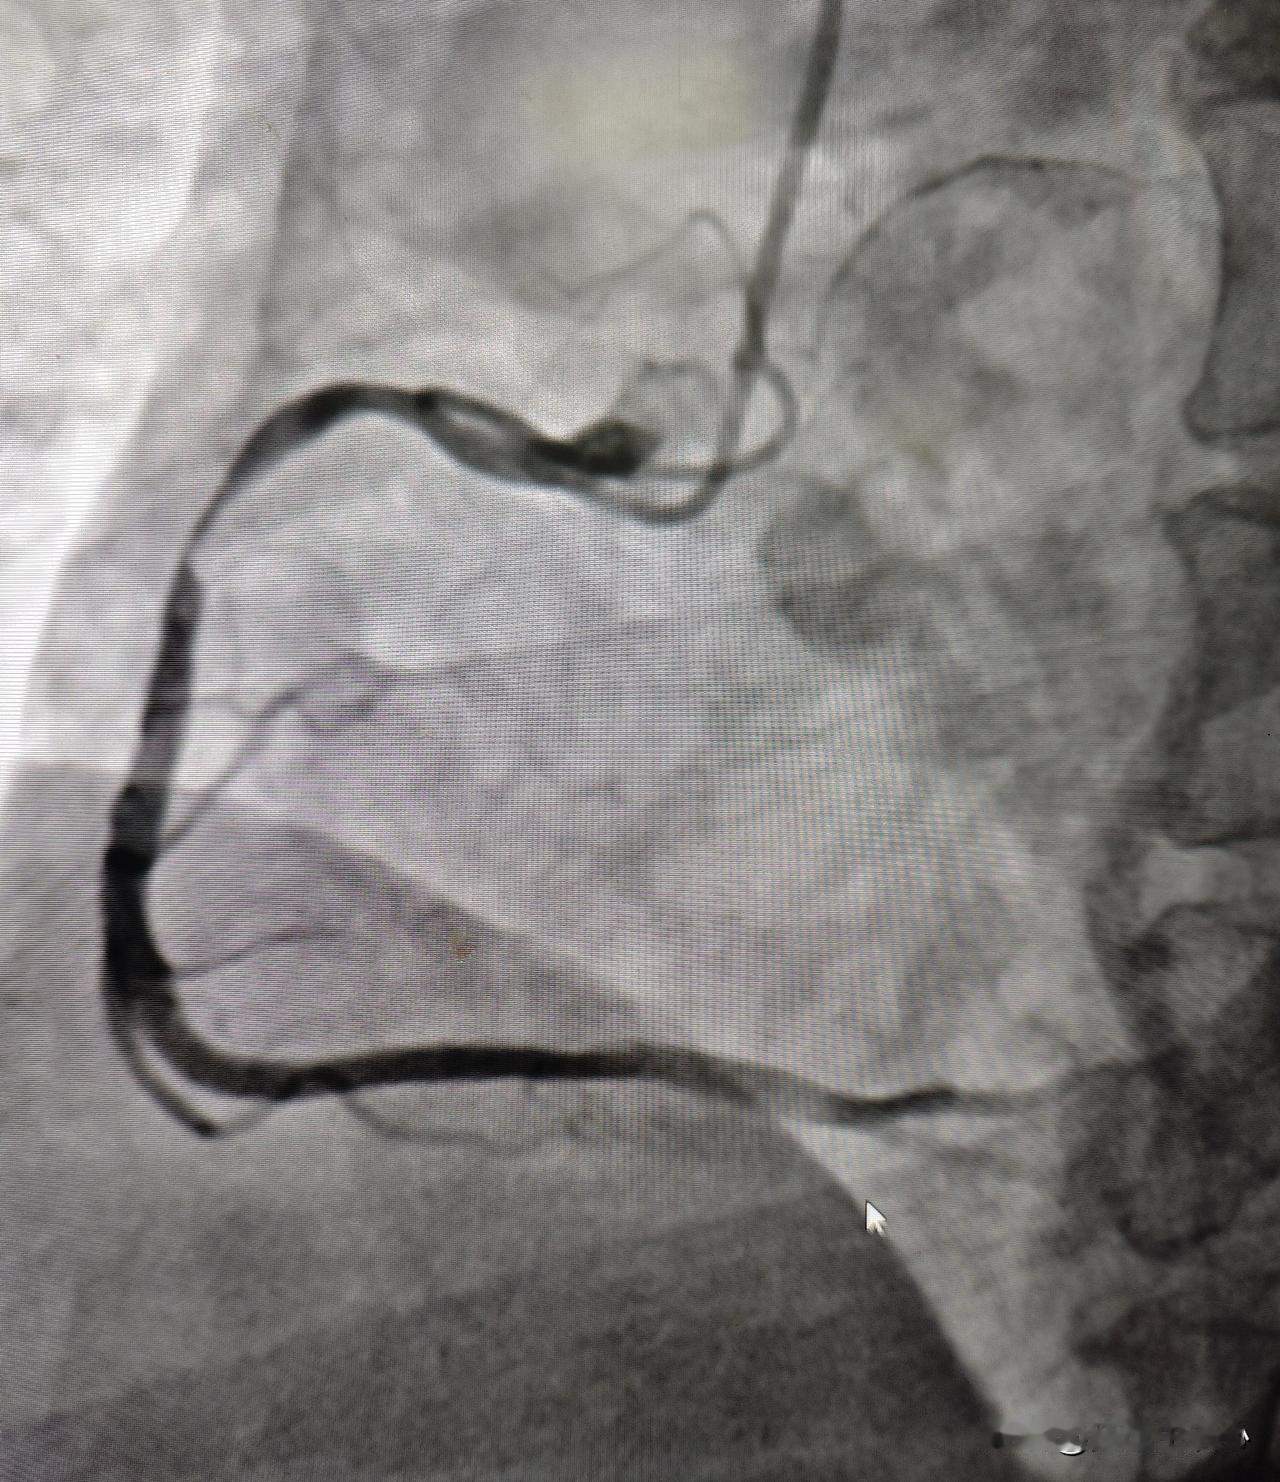

这是一位52岁肝硬化晚期患者1天抽出来的腹水,减轻了患者腹部压力,患者说:“好久没睡过这么安稳的觉了。”我是肝病介入张峰教授,深耕肝病领域30多年,今天这些都是我宝贵的经验精华,肝友们一定要看完! 肝硬化腹水只能抽吗?当然不!抽腹水只是治标不治本,像这位患者刚来的时候,肝硬化失代偿期(即晚期),白蛋白只剩下27,腹水10多公分,咱利尿、抽腹水,是为了减轻痛苦,更是为下一步治疗铺路! 要想彻底消除腹水,必须抓病根!比如乙肝肝硬化,就要从“抗病毒+软化肝脏”着手,恢复肝功能,提升白蛋白!白蛋白上去了,腹水才可能从根上消除!如果你或家人正在被腹水折磨,可别只治并发症,一定要重视原发病,找对方法、双管齐下,咱们战胜肝硬化的把握也更大一些!